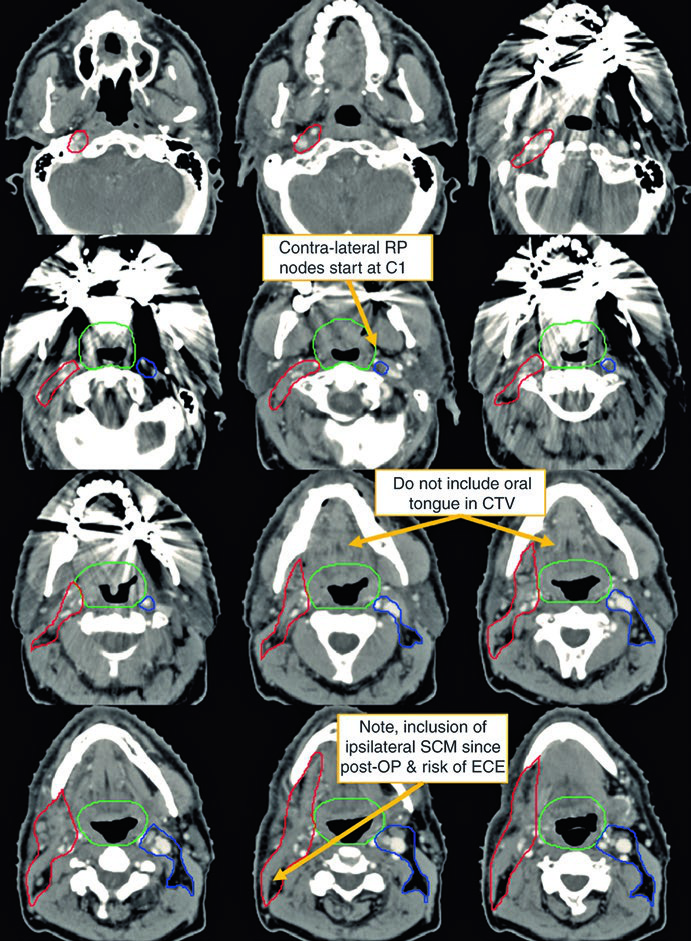

O primeiro caso ilustra um homem de 62 anos com primário oculto TxN2a, submetido a tonsilectomia bilateral e esvaziamento cervical direito, que revelou um único linfonodo de 4,6 cm no nível II.

Observe a diferença entre o delineamento no pescoço operado (ipsilateral) e o contralateral. O CTV66Gy (vermelho) cobre o leito cirúrgico de alto risco; o CTV54-60Gy (verde) cobre as mucosas faríngeas em risco de abrigar o primário; e o CTV54Gy (azul) cobre o pescoço contralateral profilaticamente. Essa assimetria reflete o princípio de escalonar a dose conforme o risco real.